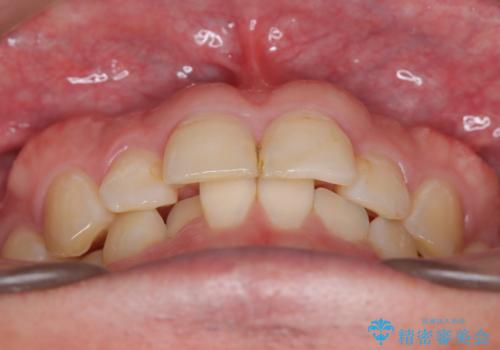

- 定期的に当院に通院されている患者様ですが、前歯が欠けてしまい困っているとのことで来院されました。その日は応急でレジン充填を行いましたが、上下顎前歯の当たりが強くまた同じように欠けてしまう可能性が高いと考え、セラミッククラウンにて修復した一例です。前歯一歯の色合わせは非常に難しく、特に周囲の歯に模様がある場合難易度が上がります。そのため、今回は当院のセラミッククラウンの中で最もランクの高いものを選択し、非常に綺麗に仕上げることができました。

最終クラウンを作る前に仮歯をご用意し、色調や形を患者様とご相談します。その後、必要に応じて口腔内写真を製作ラボにお送りし、作り手の歯科技工士と情報共有をさせていただきます。症例によっては、診療室で直接患者様と技工士との打ち合わせの場を設けることもあります。